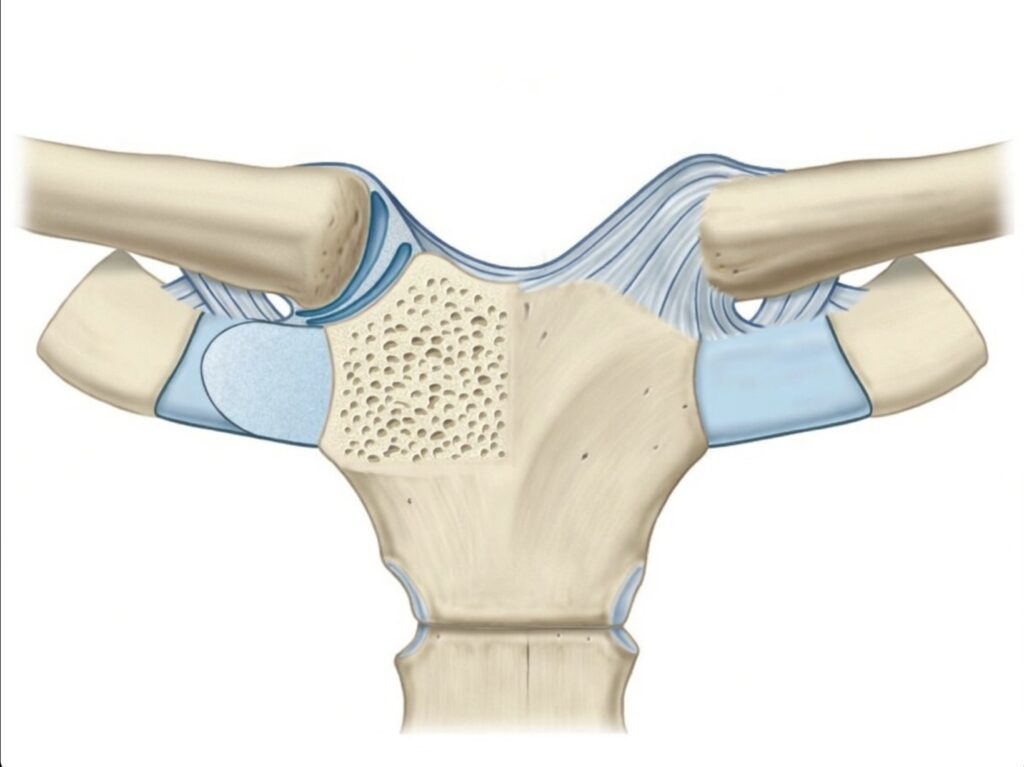

Las superficies articulares que participan en esta unión presentan diferencias marcadas en cuanto a tamaño, forma y orientación. La superficie esternal es relativamente pequeña y poco profunda, mientras que la superficie clavicular es más amplia y de configuración irregular. Esta falta de correspondencia geométrica impide un encaje perfecto entre ambas, lo que haría inestable la articulación si no existieran estructuras compensadoras.

Por esta razón, entre las superficies óseas se interpone un disco articular de fibrocartílago, cuya función principal es mejorar la congruencia, distribuir las cargas y amortiguar las fuerzas transmitidas desde el miembro superior hacia el esqueleto axial. Gracias a este disco, la articulación puede mantener estabilidad a pesar de su escasa congruencia ósea.

Desde el punto de vista estructural, se trata de una articulación sinovial de tipo selar o en silla de montar. Esta clasificación se debe a que las superficies articulares presentan curvaturas recíprocas en dos planos perpendiculares, lo que permite movimientos en distintos ejes. Sin embargo, la amplitud de estos movimientos es limitada, ya que la estabilidad es prioritaria frente a la movilidad, dada la función de sostén y transmisión de fuerzas que cumple esta articulación.

Las superficies articulares de la articulación esternoclavicular se encuentran revestidas de cartílago, lo que reduce la fricción, facilita el deslizamiento y protege los extremos óseos frente al desgaste mecánico. Cada una de estas superficies posee características morfológicas específicas que condicionan el comportamiento funcional de la articulación.

En el esternón, la superficie articular se localiza en la incisura clavicular del manubrio, situada en su porción superolateral. Esta superficie es oblonga y alargada transversalmente, con una orientación oblicua que va de medial a lateral y de superior a inferior. Dicha orientación permite que la clavícula pueda realizar movimientos de elevación, descenso y desplazamiento anteroposterior durante la movilidad del hombro.

El primer cartílago costal participa de manera complementaria en la articulación. Presenta una pequeña superficie articular de forma triangular, dispuesta horizontalmente en su región medial y superior. Esta superficie se continúa sin interrupción con la superficie articular del esternón, lo que explica que funcionalmente ambos elementos actúen como una sola unidad esternocondral. La inclusión del cartílago costal contribuye a aumentar la superficie de contacto y a reforzar la estabilidad inferior de la articulación.

La extremidad medial de la clavícula presenta una morfología compleja que refleja la adaptación funcional de este hueso a las exigencias mecánicas de la articulación. En lugar de una única superficie articular simple, la clavícula ofrece dos carillas articulares continuas entre sí. Una de ellas es vertical y está orientada medialmente y ligeramente hacia abajo, mientras que la otra es horizontal y se sitúa inmediatamente por debajo, formando con la primera un ángulo recto.

Esta disposición en diedro permite que la clavícula se adapte a las superficies esternocondrales, aunque sin lograr una congruencia completa. Además, la clavícula sobresale superiormente con respecto al borde del manubrio esternal, lo que condiciona la dirección de las fuerzas transmitidas y explica la necesidad de potentes medios de unión ligamentarios.

El ángulo diedro saliente de la clavícula se apoya sobre el ángulo diedro entrante formado por el esternón y el primer cartílago costal. Sin embargo, debido a la diferencia de curvaturas y extensiones entre ambas superficies, el contacto óseo es imperfecto. Esta incongruencia estructural justifica la presencia imprescindible del disco articular, cuya función es compensar estas irregularidades y garantizar un funcionamiento armónico de la articulación.

El disco articular es una estructura de fibrocartílago interpuesta entre las superficies óseas, cuya forma recuerda a una lente cóncavo-convexa. Su periferia es más gruesa que su región central, lo que le permite adaptarse mejor a las variaciones de presión que se producen durante los movimientos del hombro. En algunos individuos, el centro del disco puede presentar una perforación, sin que ello comprometa necesariamente la función articular.

Este disco se fija firmemente a la cápsula articular por sus caras anterior y posterior, lo que asegura su estabilidad durante los desplazamientos de la clavícula. Superiormente se inserta en la clavícula e inferiormente en el primer cartílago costal, estableciendo una conexión sólida entre ambos elementos.

Desde el punto de vista funcional, el disco articular cumple varias funciones esenciales: mejora la congruencia entre superficies articulares desiguales, divide la cavidad articular en compartimentos funcionales, absorbe y distribuye las fuerzas transmitidas desde el miembro superior al tórax y contribuye de manera decisiva a la estabilidad global de la articulación esternoclavicular.